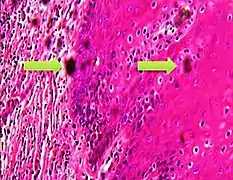

In microscopy, an artifact is an apparent structural detail that is caused by the processing of the specimen and is thus not a legitimate feature of the specimen. In light microscopy, artifacts may be produced by air bubbles trapped under the slide's cover slip.[1]

A crush artifact is an artificial elongation and distortion seen in histopathology and cytopathology studies, presumably because of iatrogenic compression of tissues. Distortion can be caused by the slightest compression of tissue and can provide difficulties in diagnosis.[2][3] It may cause chromatin to be squeezed out of nuclei.[4] Inflammatory and tumor cells are most susceptible to crush artifacts.[4]